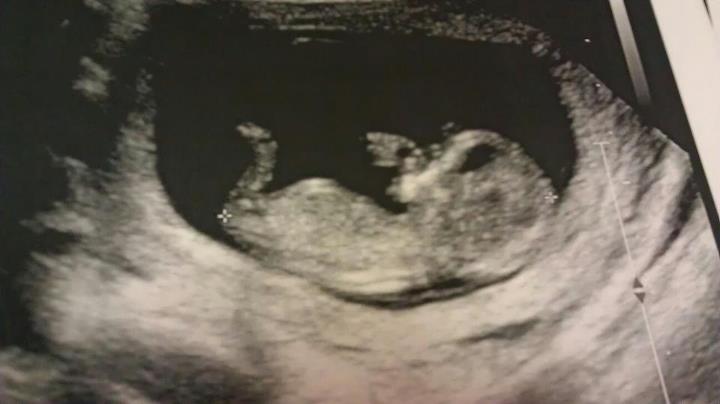

Hi all, im new here. Attaching two us photos from 12-13weeks. Can any one give me their guesses? Attachment 1737Attachment 1738

I think the forehead is boyish in the first pic, but the chin is a lil pointed, that is girlish? I'm sorry, I'm not sure!

I think girl based on the overall baby shape and head, theres no sign of a protruding nub so yeah girl good luck hun

Thinking girl based on the skull theory.

Maybe girl? (skull)